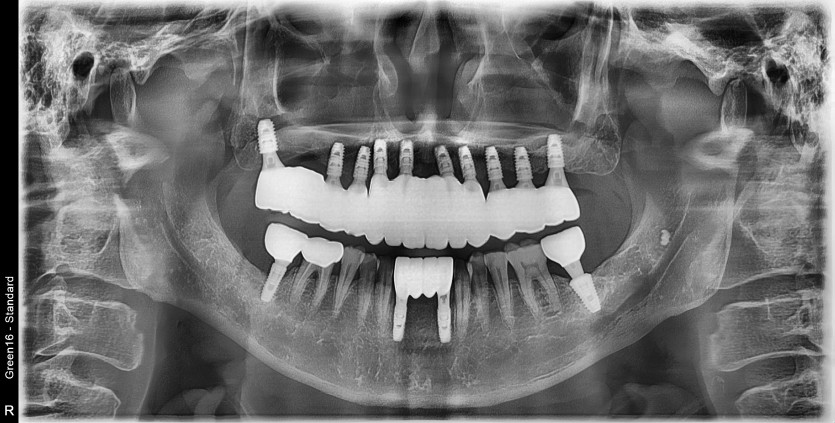

만 65세 상악 전체 임플란트 증례 (하악 전치부)

상악 전체 임플란트 증례입니다.(하악 전치부)

12개의 임플란트로 완성하였습니다.